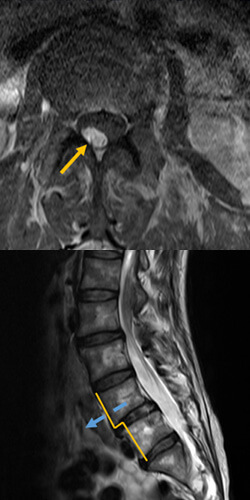

骨盤周りの筋肉はこり固まり、まるでコルセットをしているかのように腰回りに筋肉のこぶができていました。整形外科でレントゲンを撮ったところ、「脊柱管狭窄症」「腰椎すべり症」との診断。「手術しかないよ」と言われましたが、踏み切れず。薬を服用しながら車イス生活を送っていました。

重度の椎間板ヘルニアに悩まされていました。

病院では椎間板ヘルニアと診断された。

「足を引きずらないと歩けない」「脚が痛くて夜も眠れない」「まっすぐ歩けない」など…

重度の椎間板ヘルニアで悩んでいました。整体・接骨院・鍼などすべて受けましたが治らず、あきらめかけていました。整形外科では、神経ブロック注射を2回打っても改善の兆しはなし。

ヘルニアを摘出するしかないと思い、あきらめ半分で手術の専門病院に足を運ぶと…

レントゲンとMRIの検査だけで「ヘルニアがあるから手術ね」と告げられてしまったんです。

「脊柱管狭窄症」「腰椎すべり症」との診断を受けました。

半年前から右太ももとふくらはぎが痛くなり、

脚を引きずらないと歩けなくなりました。

時間にして、数十秒しか歩くことができないほど状態が悪かったですね。治療院や整形外科にも行きましたが症状は改善されず。

歩けない、立てない…

そんな状態が続いて不安だけが募っていきました。

大学病院で検査を受けると「管内脂肪増殖による脊柱管狭窄症」であることが判明。

ブロック注射や神経障害性疼痛薬(リリカ)で様子を見るも、激痛が収まることはありませんでした。

それどころか症状が悪化し、最終的には寝たきり状態になってしまいました。